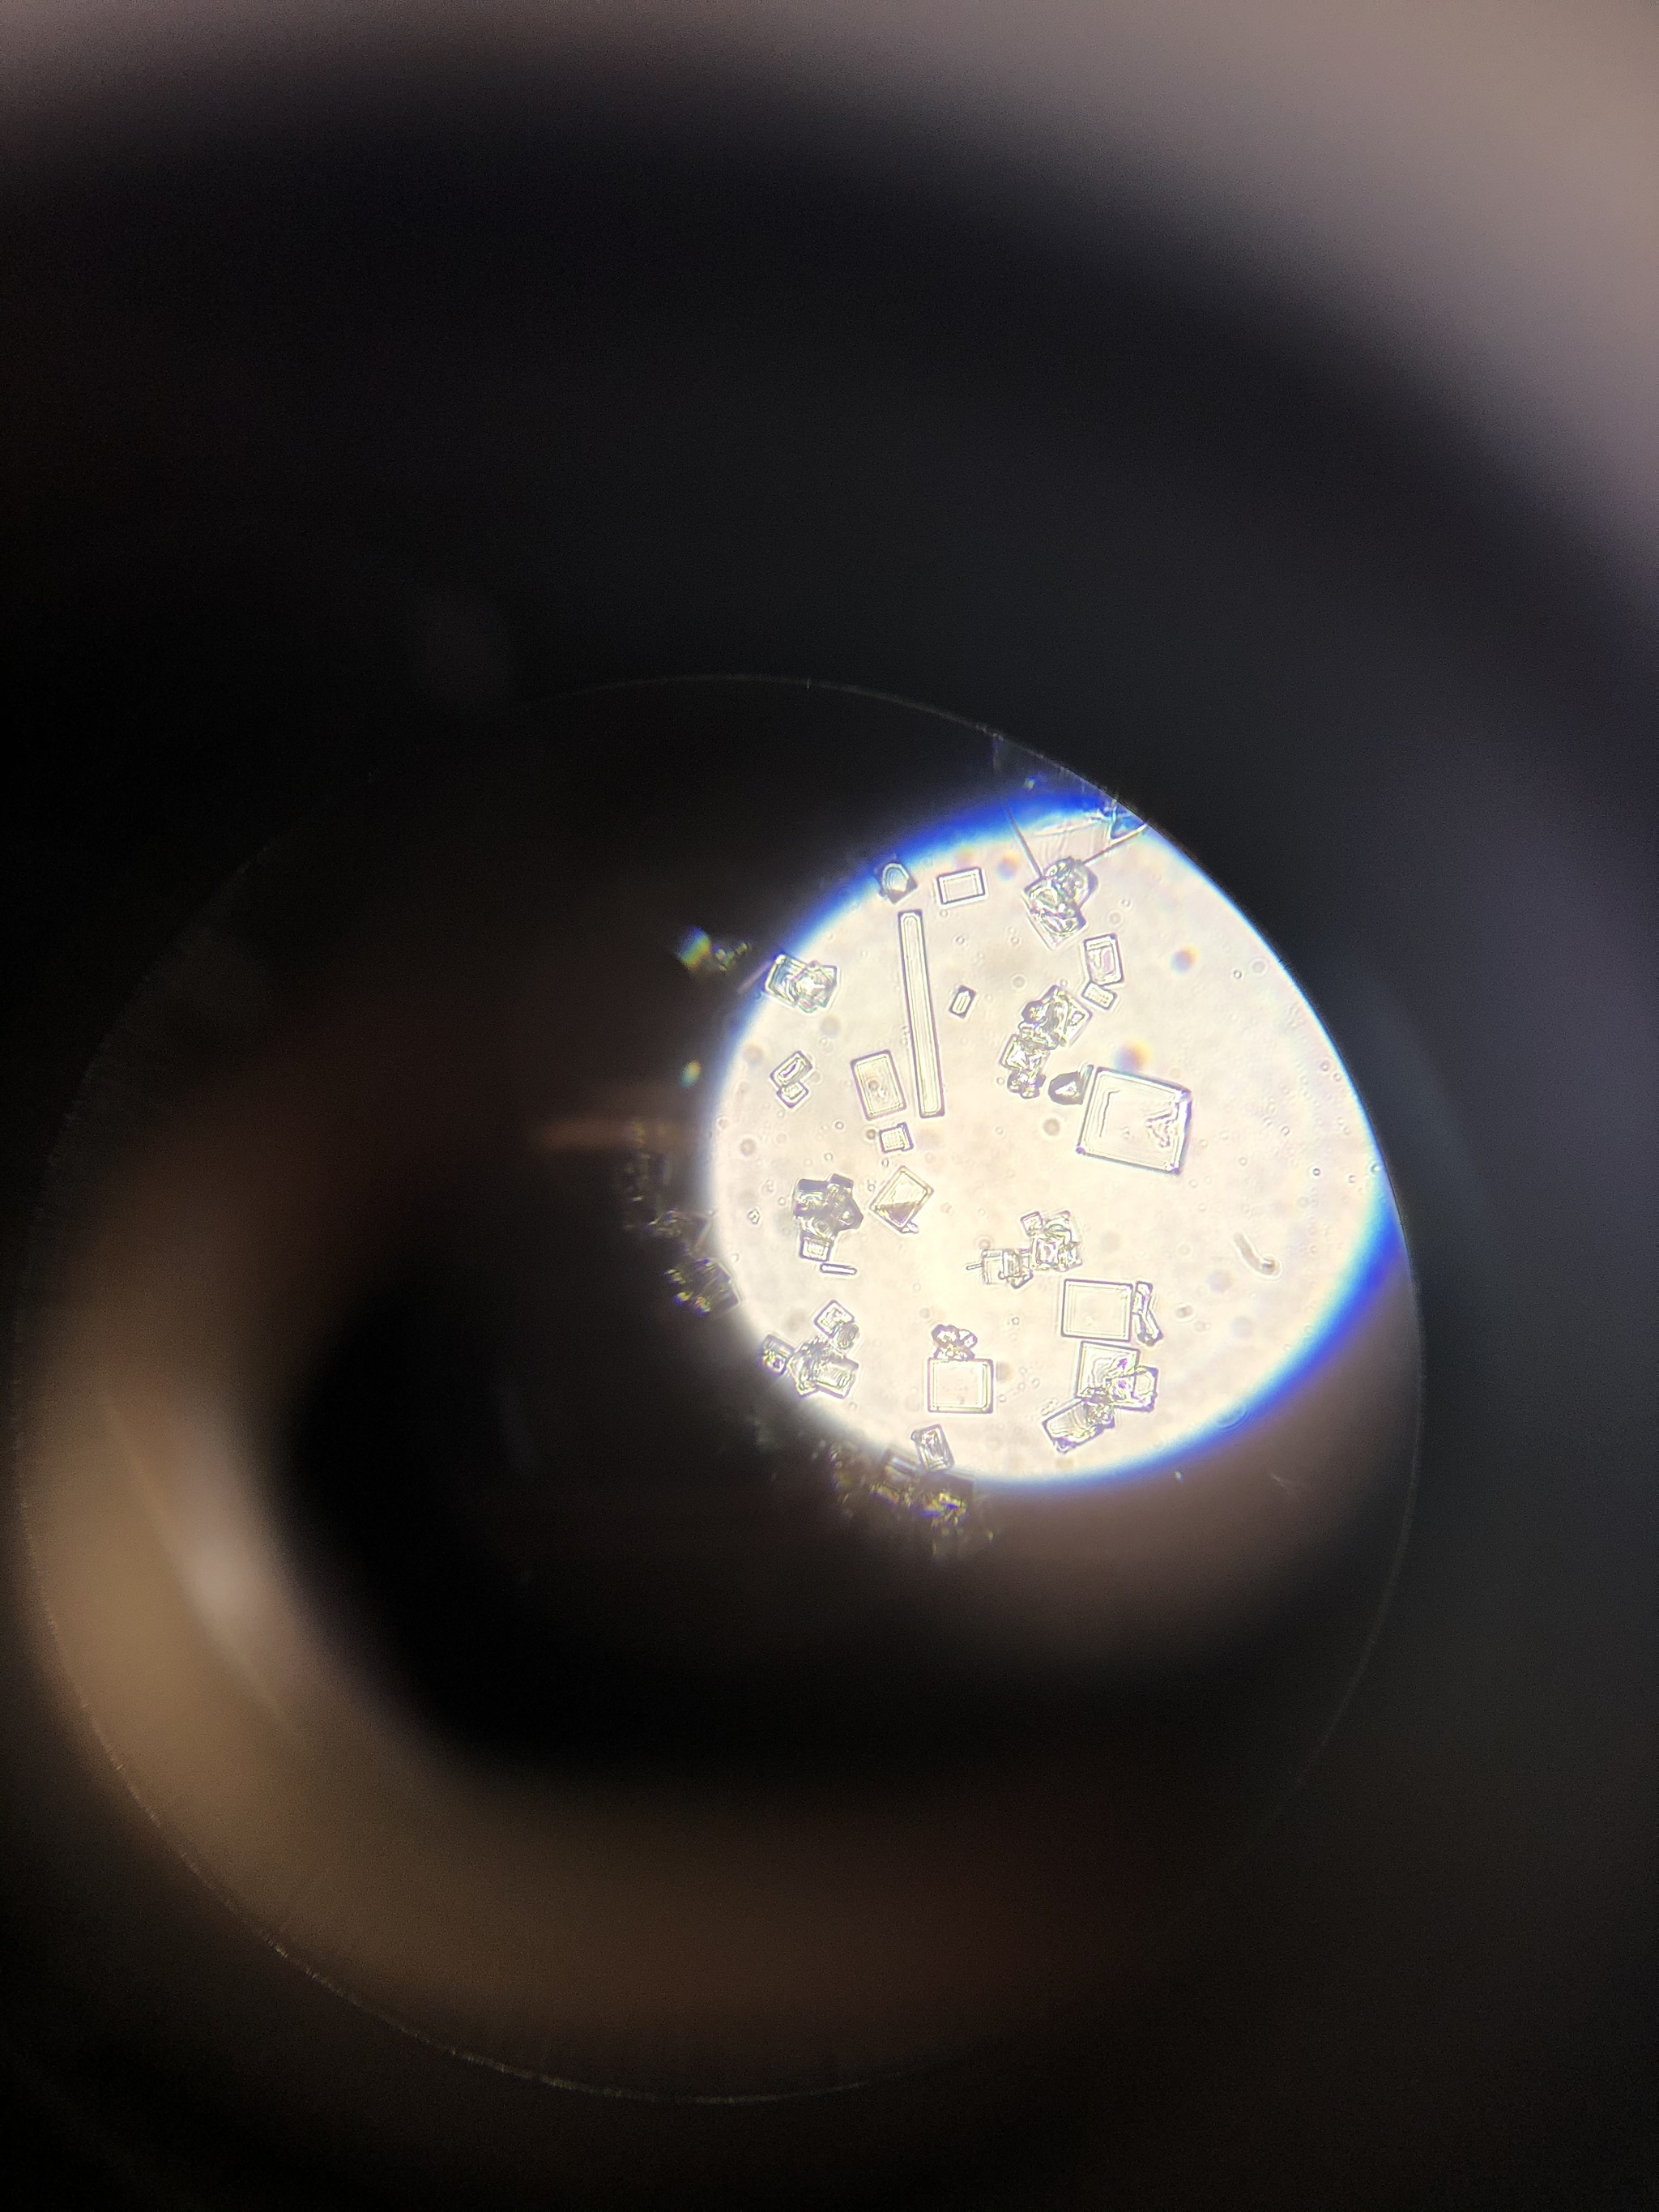

Фууух, после такого длинного, но важного предисловия мы наконец-то добрались до фоточек. Если не устали - читаем дальше!

Как вы уже поняли, коварство вируса заключается в поражении ДНК клетки. И когда это случается - конечно же ядро (хранилище ДНК) видоизменяется.

Все фото ниже - это женские урогенительные мазки. Какой тип герпеса - ВПГ 1 или 2 достоверно сказать не могу, да и значения на самом деле это не имеет.

Сравните ядра здоровых клеток (точечные, бордовые стрелки) и ядро клетки, пораженное вирусом. Оно невероятно огромное, сложенное, кривое и с какими-то лопастями. Да и сама клетка гигантская (голубой ореол вокруг ядра).

Вот эта клетка мне очень нравится. Называю ее "лодочка", почему-то напоминает ядром каноэ. Вирус закрутил его в спираль. Конечно, в практическом смысле толку от этой клетки организму не особо много.

Ниже еще один вариант поражения, снова гигантская клетка и ядро с несколькими лопастями. Как вы уже догадались наверное, подобные изменения ядра являются довольно характерным признаком для вирусного поражения.

Общий фон тоже довольно воспалительный и не здоровый, но на него сейчас внимания обращать не нужно. В случае обнаружения всевозможных аномалий и отклонений в мазках - об этом стоит упомянуть в бланке анализа, а гинеколог дальше сам решит что делать с этой информацией и как лечить пациента.

Бордовой стрелкой напоминаю еще раз как выглядят нормальные ядра.

Как видите, вариантов поражения множество, но в любом из них становится сразу ясно, что до нормы тут далеко.

А тут вообще красивый комплекс попался. Некоторые ядра как будто закольцованы, со множеством лопастей, гигантские.

Да и общий фон не в порядке: большое количество лейкоцитов, говорящих о воспалении, скудная нездоровая флора...

Честно говоря уже не помню точно, но есть подозрение что многие из этих фото от одного пациента - уж больно общая картина схожая.